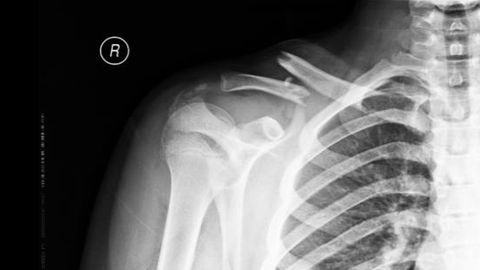

Rūdolfu ar lauztu atslēgas kaulu Bērnu klīniskā universitātes slimnīca (BKUS) aizsūtīja atpakaļ uz Jēkabpili, kur kaulu saskrūvēja ķirurgs. Mājās aizsūtīja arī Madaru, kuras mamma atrada ķirurgu caur Facebook. Identiski notika ar Ralfu. BKUS šīs traumas iesaka fiksēt ortozē un no 360 atslēgas kaula lūzumiem pērn operēts tikai viens. TVNET+ skaidro, kuros gadījumos to operē un kāpēc vecāki pašrocīgi meklē ķirurgus arī privātās iestādēs.